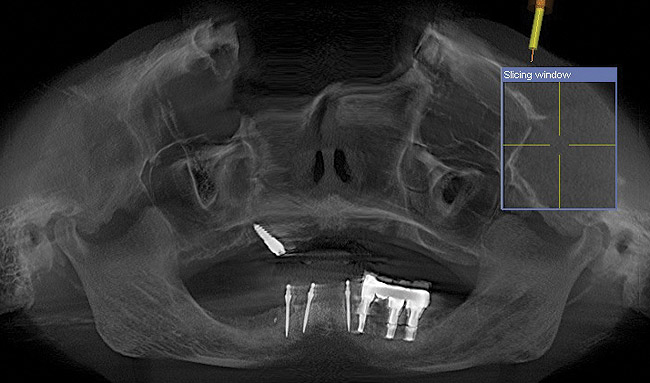

The patient was scanned with a cone beam CT scan while wearing a radiopaque scanning appliance based on her new treatment denture. Horizontal bone augmentation was confirmed radiographically, and both grafted sinuses resulted in satisfactory bone quantity for implant placement. Vertical augmentation was not attempted because of the patient’s unwillingness to forego her removable prosthesis for any period of time. Therefore, shorter implants were treatment-planned, resulting in the placement of eight implants, rather than fewer—such as six—implants, to support a full-arch fixed prosthesis. Because adequate bone and keratinized mucosa were present, a flapless, computer-guided implant insertion was performed (Figure 18). After removal of the surgical guide, placement of all eight implants could be inspected (Figure 19). Post-placement periapical radiographs are shown in Figure 20 and Figure 21.

Figure 18  Flapless, computer-guided implant insertion.

Figure 18

Figure 19  Removal of surgical guide enabled inspection of implant placements.

Figure 19

Figure 20  Post-placement periapical radiographs.

Figure 20

Figure 21  Post-placement periapical radiographs.

Figure 21

Figure 24  Postoperative CT scan demonstrated horizontal bone regeneration.

Figure 24

Figure 25  Postoperative CT scan demonstrated horizontal bone regeneration.

Figure 25